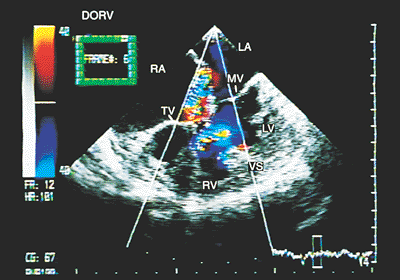

Right Ventricular Double Outlet

In the right ventricular double outlet both great arteries arise mainly or completely from the right ventricle. Any type of A–V connection can coexist. The position of the vessels is variable. When they are side-to-side or the aorta is anterior, the emergence of the vessels is parallel. When the aorta is posterior and right, the great arteries cross in space. Often the underlying anomaly is tetralogy of Fallot with aortic overriding of >50%.

The principal findings observed with transesophageal echocardiography are discussed in the following paragraphs.

Overriding of >50% of the posterior vessel over the interventricular septum is evident in recordings of both transverse and longitudinal planes (Fig. 8.2.52). The connection of both vessels with the right ventricle can be observed in longitudinal images (Figs. 8.2.53 and 8.2.54). When only monoplanar recordings can be obtained, multiple sections at various levels should be visualized to demonstrate that the great arteries are located on the same side of the interventricular septum (Fig. 8.2.55).

The examination of the ventricular outflow tracts should include images in transverse and longitudinal planes to look for subpulmonary obstructions and to investigate the relationship between the ventricular septal defect and the great vessels.

Color Doppler study demonstrates that the flow that crosses the ventricular septal defect is directed preferentially toward the vessel with which the defect is associated. The defect can be subaortic or subpulmonary, can be related to both arteries, or can have no relation with either (Fig. 8.2.56).